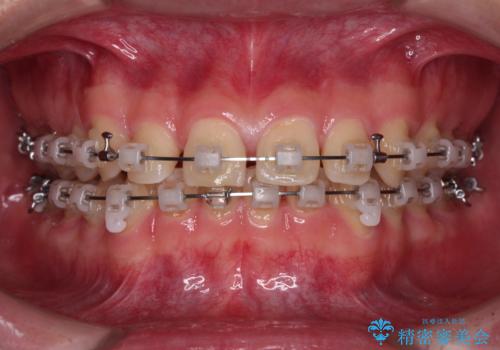

隙間とデコボコを治したい ワイヤー装置による矯正治療

- 矯正装置

- クリアブラケット

- 2年2ヶ月

- 前歯のデコボコと隙間を気にして来院された患者様です。

治療手段としてはワイヤー装置でもインビザラインでも可能でしたが、インビザラインの自己管理は自信がないとのことで、ワイヤー矯正により隙間を閉じていくこととしました。

隙間の原因は舌の突出癖であったので、舌癖改善のためのトレーニングを指導しながら治療を進めて行くこととしました。

舌の突出癖がなかなか改善されず、治療開始時よりも隙間が大きく開いてしまう時期がありましたが、最終的にしっかりと閉じて終了することができました。